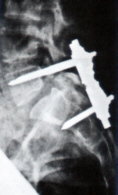

Ein Fixateur hält die Wirbel in der richtigen Stellung.

Der auf dem Bauch gelagerte Betroffene wird zunächst mit sterilen Tüchern abgedeckt und das Operationsgebiet desinfiziert. Die Länge des Hautschnitts hängt davon ab, über wie viele knöcherne Etagen sich das Wirbelgleiten erstreckt. Nach erfolgtem Hautschnitt werden zunächst vorsichtig die Rückenmuskeln von der Wirbelsäule abgeschoben, um diese übersichtlich darzustellen. Falls notwendig, werden nun zunächst Anteile der Wirbelbögen und/oder der Wirbelgelenke entfernt, um den Platz für die Nerven zu vergrößern. Dann schließt sich der eigentliche stabilisierende Teil des Eingriffs an: Durch die Wirbelbögen werden auf jeder Seite und auf jeder zu behandelnden Etage, unter ständiger Röntgenkontrolle, Metallschrauben bis in die Wirbelkörper gedreht. Die aus den Wirbeln ragenden Enden der Schrauben werden dann auf jeder Seite jeweils durch einen längs verlaufenden Metallstab miteinander verbunden. Optimalerweise werden die einzelnen Wirbel vor der Fixierung, durch Zug an den einzelnen Schrauben, in eine anatomisch möglichst günstige Position gebracht. Die beiden Längsstäbe werden abschließend durch eine metallene Querverbindung aneinander fixiert, um eine möglichst gute Stabilität zu erzielen. Auf diese Weise gelingt es, die Beweglichkeit der Wirbel gegeneinander auszuschalten und die einzelnen Wirbel in eine möglichst gute Stellung zueinander zu bringen.